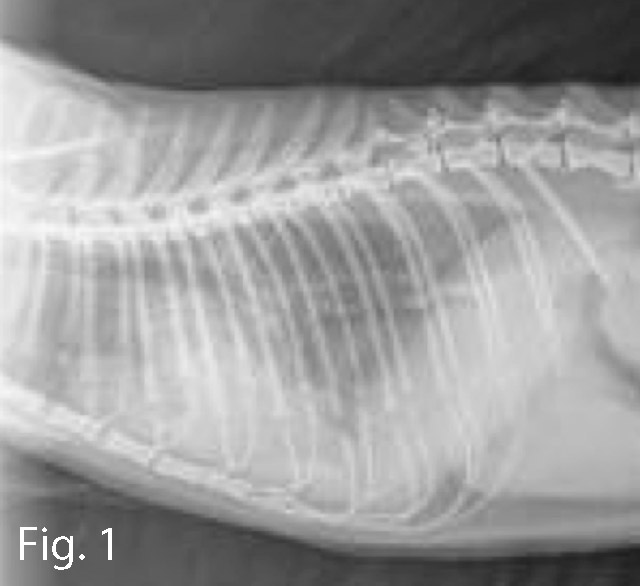

Diagnosi e trattamento di un caso di insufficienza cardiaca congestizia secondaria a miocardiopatia ipertrofica in un gatto [Luca Del Bianco, Med. Vet., Riccione] ABSTRACT: Un gatto domestico a pelo corto, maschio, di 6 anni, viene portato alla visita per dispnea ingravescente. Vengono eseguite una ecografia ed una radiografia del ...

Estrusione discale toraco-lombare in un bassotto paraplegico: una conferma della letteratura [Cecilia Patrucco, Med. Vet., Pavia] Una bassotta femmina, sterilizzata, di 7 anni è stata portata in visita per improvvisa incapacità a deambulare con gli arti posteriori. L’esame neurologico rileva un paraplegia con dolore profondo mantenuto co...